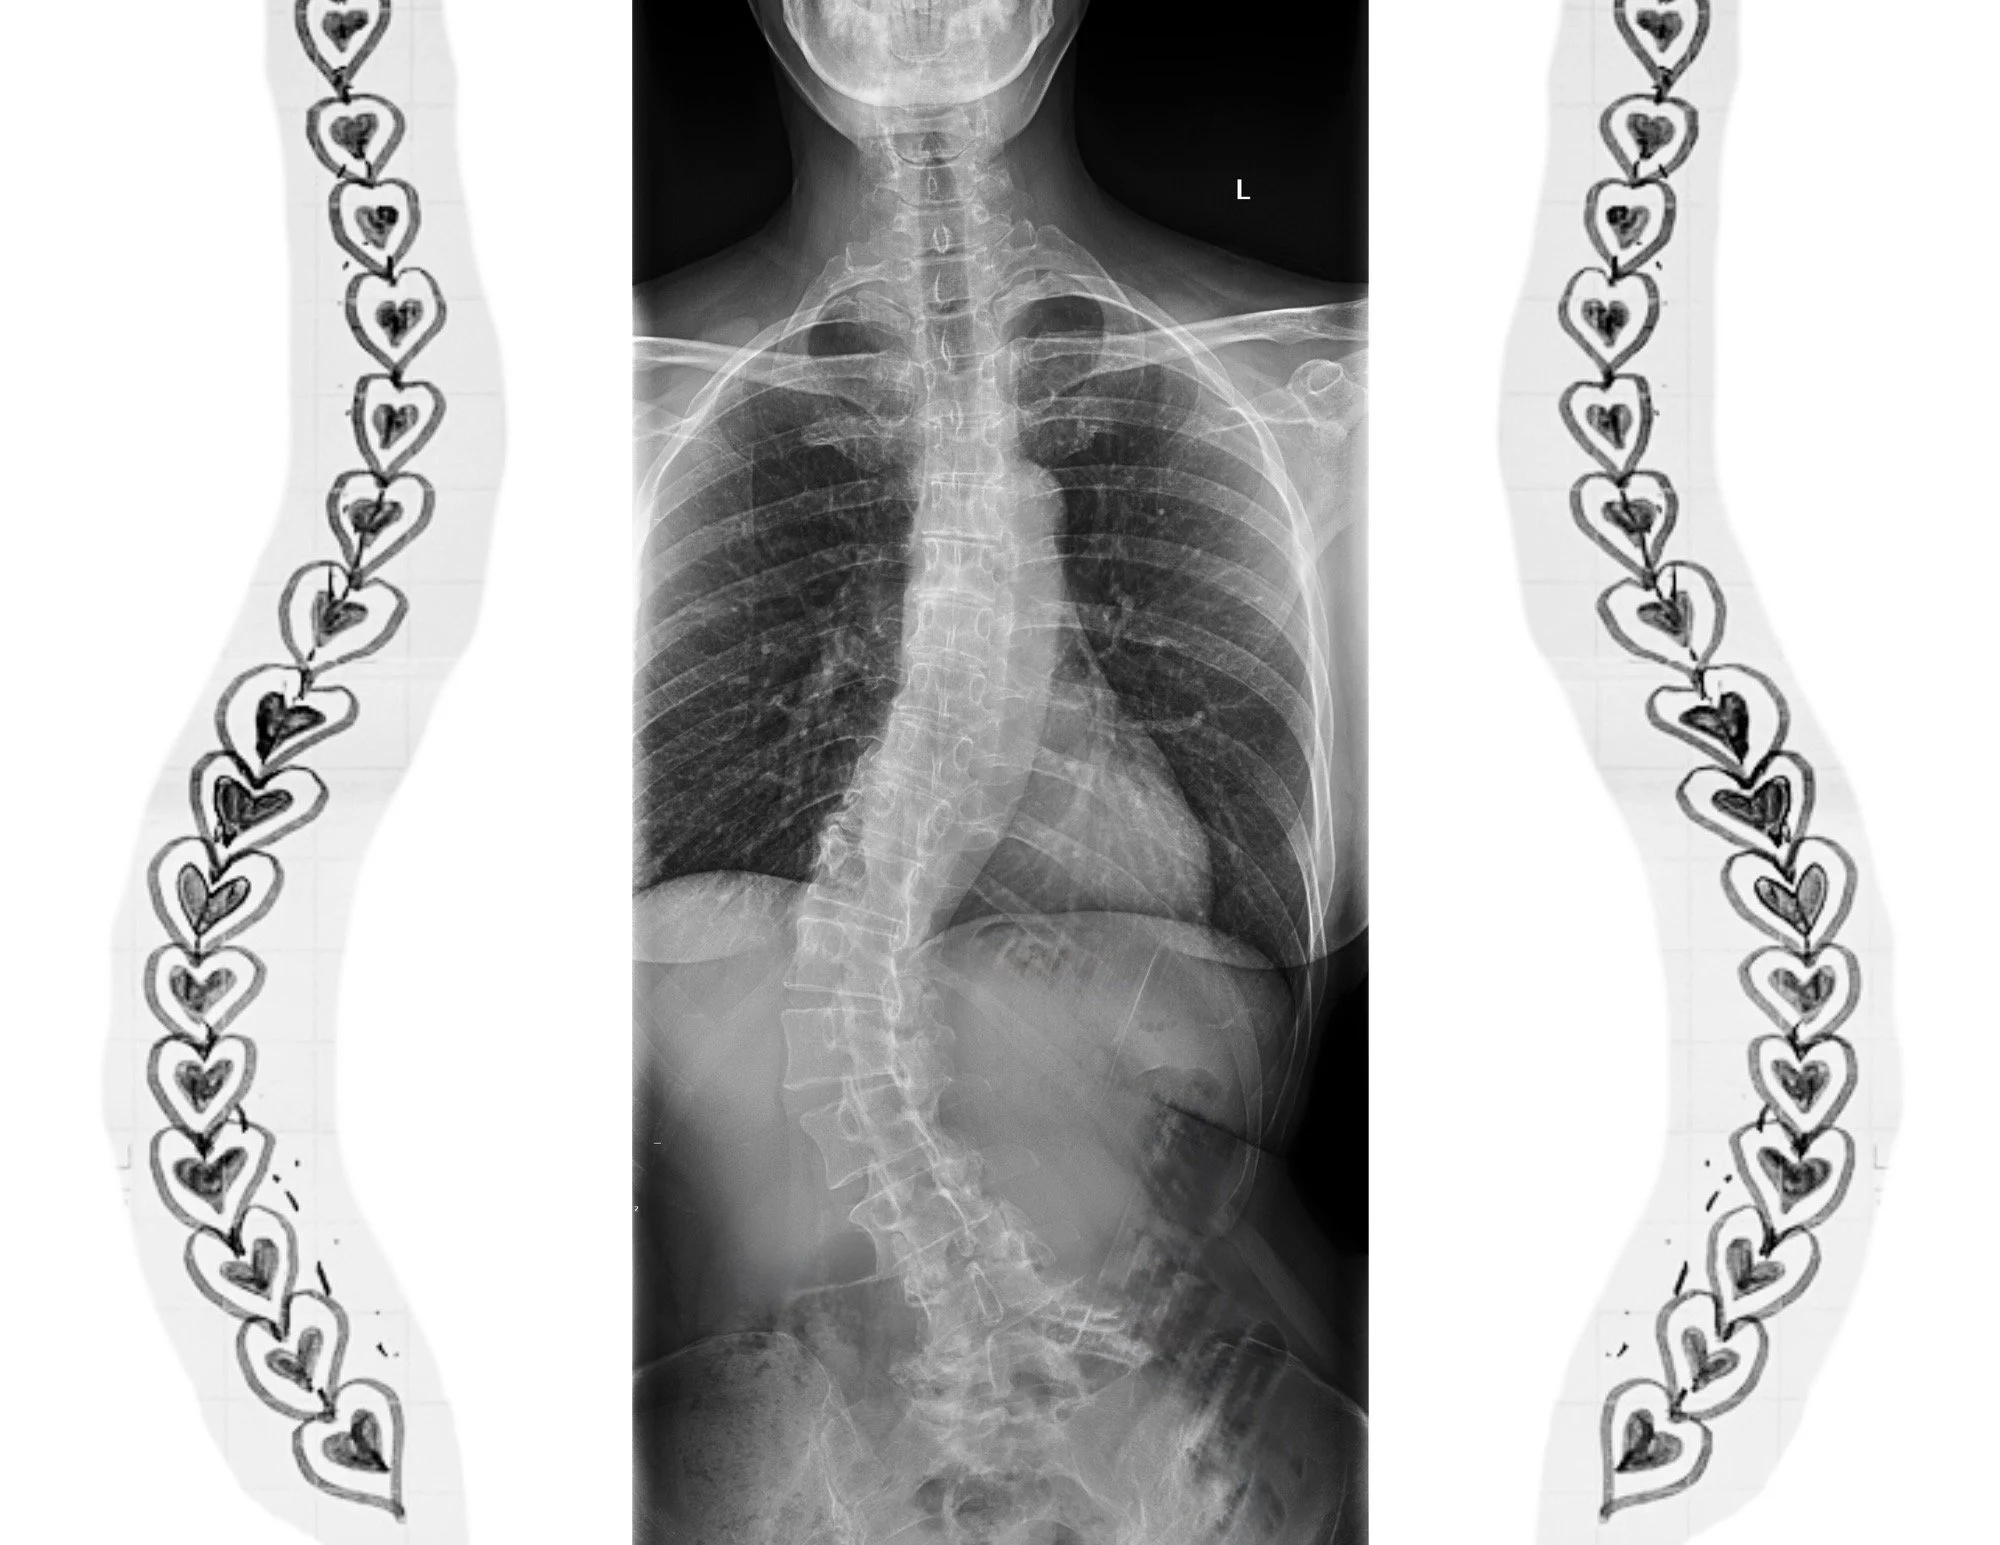

A fresh look at living well with a curvy spine…from someone who does.

Scoliosis is not a condition we would choose for ourselves or our loved one. Yet here it is, ours to navigate.

Despite what some advertisers claim, you cannot “fix” structural scoliosis. You can, however, choose to step toward scoliosis in ways that will help you thrive physically and mentally. You can learn to move, breathe, and attend to your wellbeing to support your curve, no matter your stage or age.